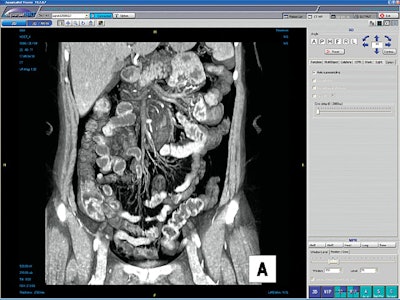

The increasingly popularity of 3D is directly correlated to the explosion of data being produced by modality scanners, in particular CT. The newer multidetector CT scanners can produce as many as 5,000 slices per study at 0.5-mm thickness. The radiologist is then faced with a dilemma: View a subset of the data and lose the benefit of the MDCT scanner, or review all the images and lose time.

Cross-sectional scans can be "summarized" by 3D viewing, reducing the number of images that require review. MPR review increases lesion detection, reduces the number of images to review, and provides images that are easier to interpret by referring physicians.

Gastrointestinal and genitourinary surgeons find 3D helpful in planning for pancreatic or renal tumor resection by analyzing vascular involvement. CT virtual colonoscopy and CT urography are being studied for future routine clinical use.

Many radiology practices still use modality workstations for 3D viewing and reconstruction, but more and more facilities are integrating 3D functionality within their PACS viewing workstations, giving radiologists immediate access to maximum intensity projection (MIP) and MPR functions and advanced 3D tools.

A facility’s PACS gives easy access to 3D studies. Trained radiologists or technologists render 3D images from CT and MR studies and return them to the PACS, where they can be archived with 2D cross-sectional images of a case and retrieved for viewing. Physicians can access the studies from a facility’s servers with privacy-protected software from their home PCs.

If you have a PACS network, Wald said, you already have a way of scrolling through MDCT images quickly, which is better than having 20 or more sheets of film, but if you have a 3D workstation on top of that, "not only can you scroll through this stuff, but you can actually look at it in a coronal image, or a sagittal image, or a volume-rendering image, or a MIP image. Those sometimes put things together in a different way.